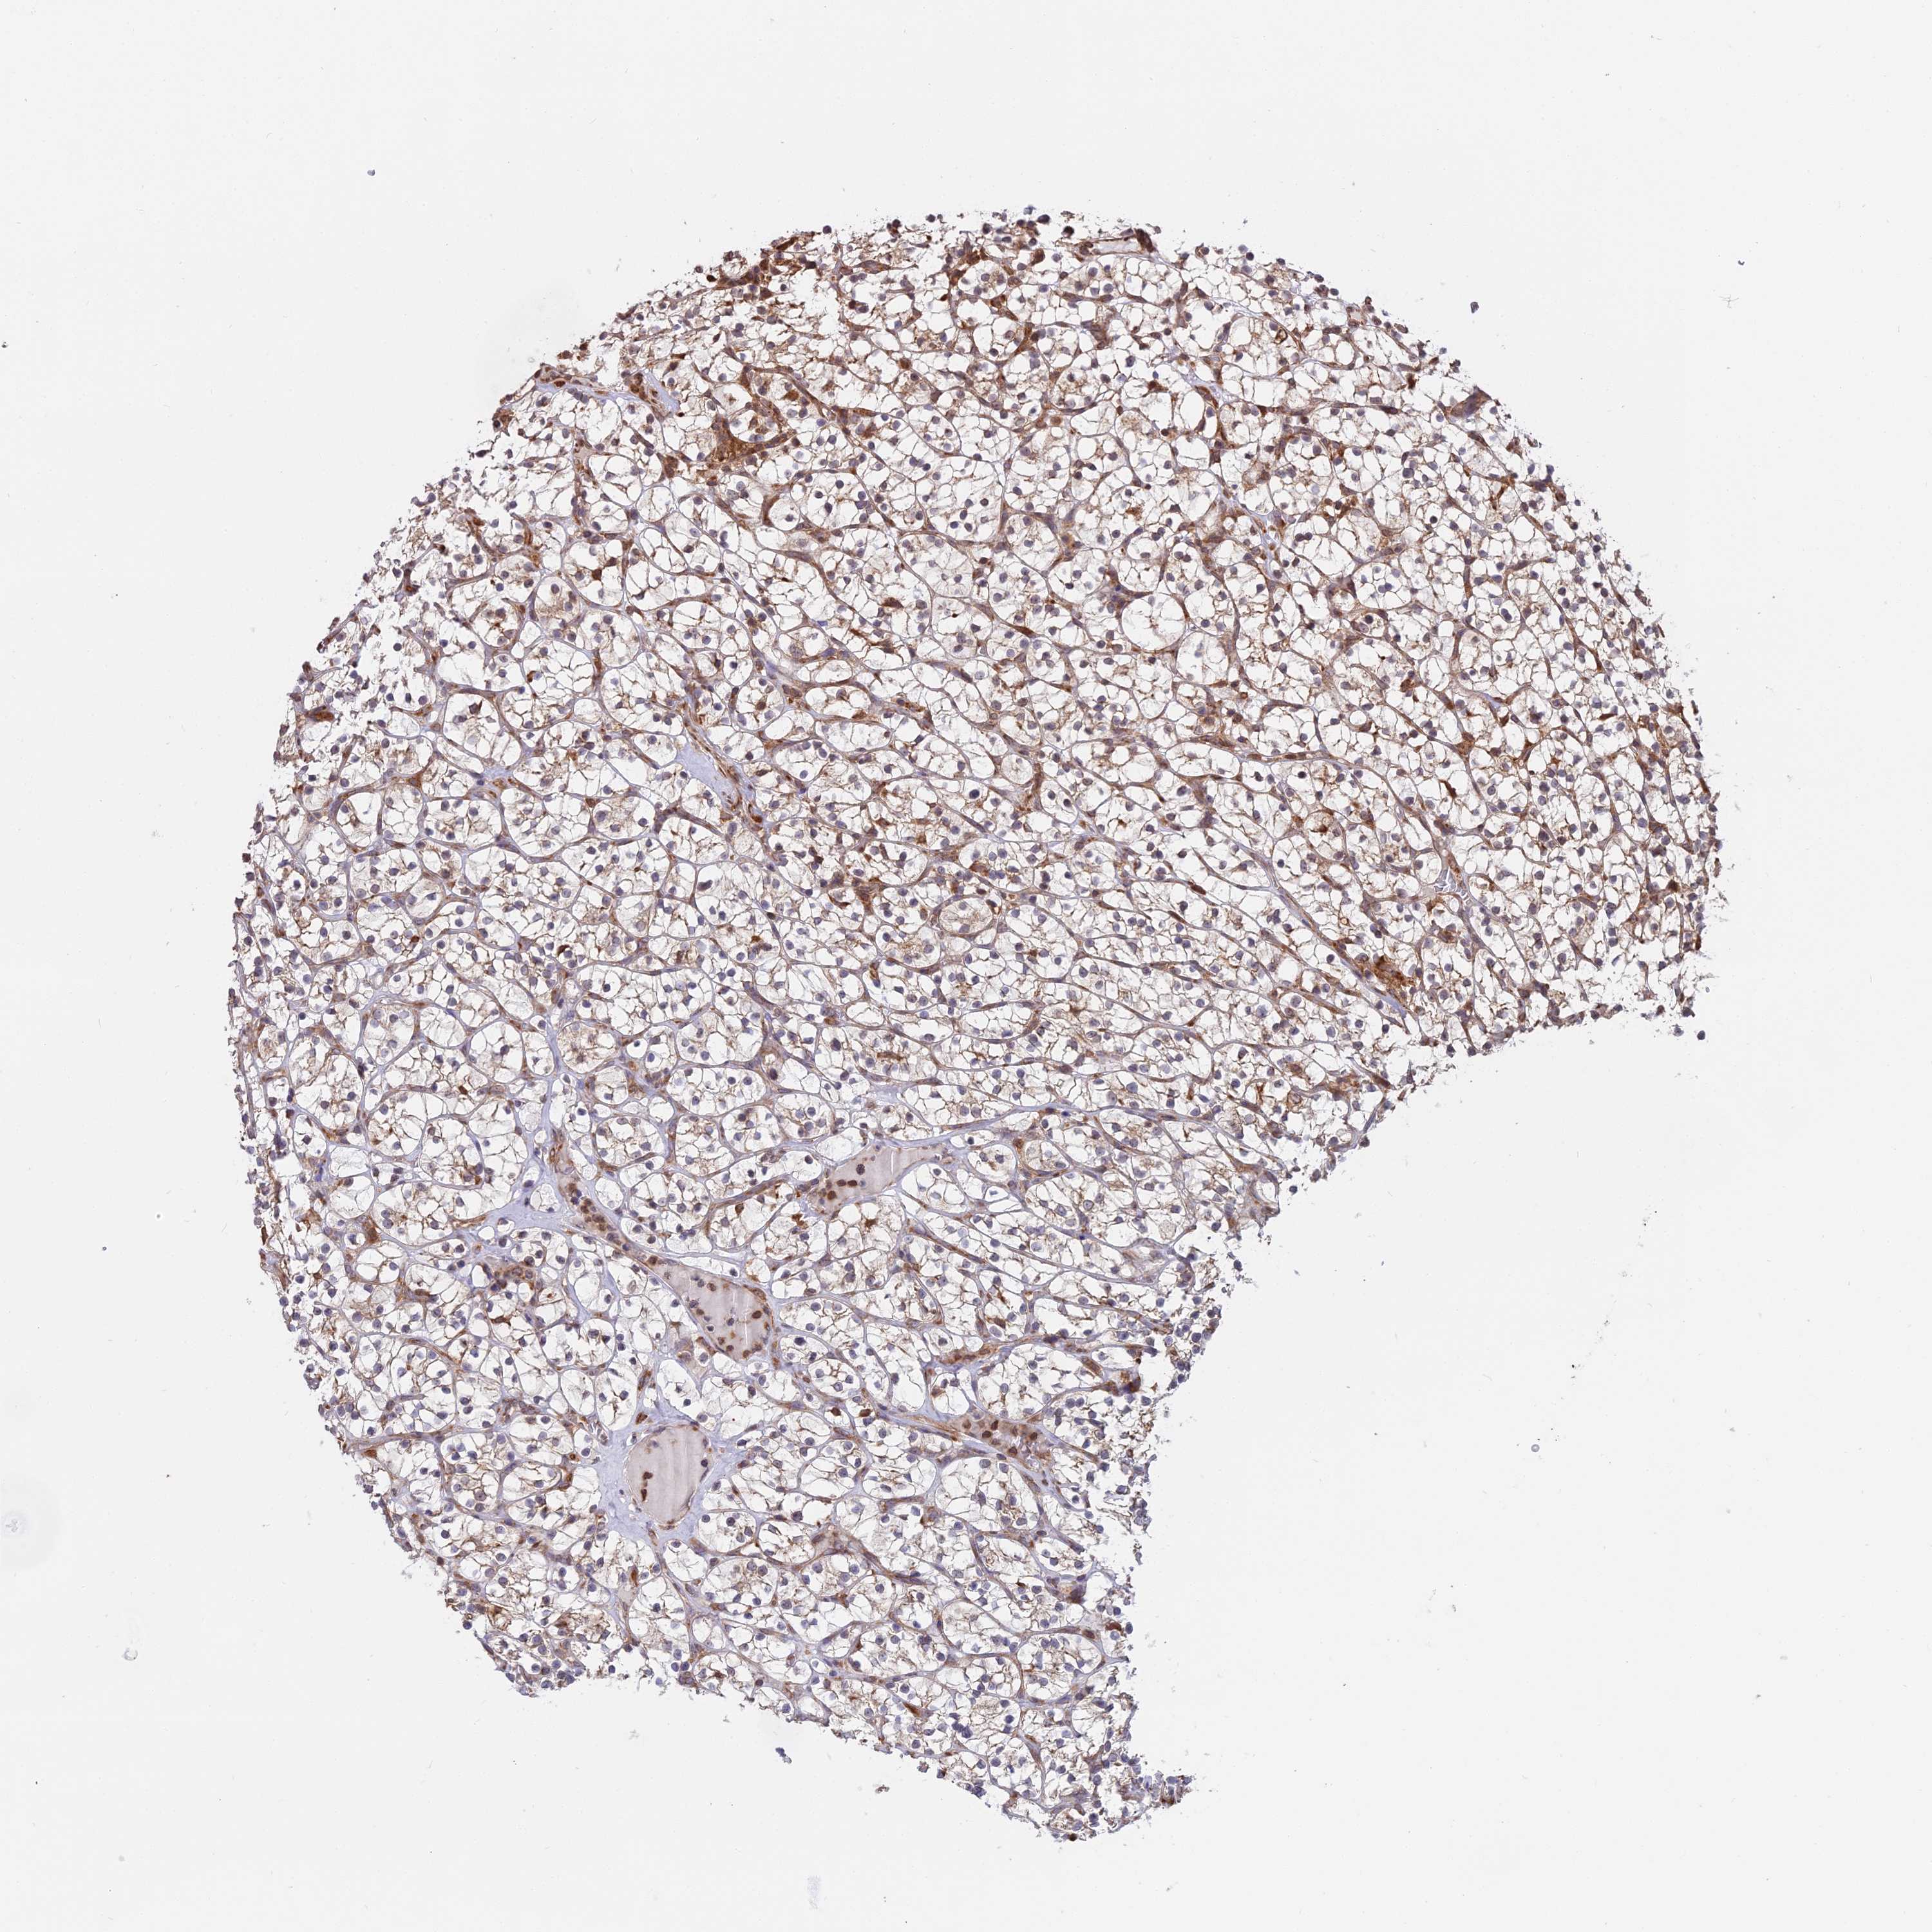

KIDNEY RENAL CLEAR CELL CARCINOMA (VALIDATION) - Interactive survival scatter ploti

The Survival Scatter plot shows the clinical status (i.e. dead or alive) for all individuals in the patient cohort, based on the same data that underlies the corresponding Kaplan-Meier plots. Patients that are alive at last time for follow-up are shown in blue and patients who have died during the study are shown in red.

The x-axis shows the expression levels (FPKM) of the investigated gene in the tumor tissue at the time of diagnosis. The y-axis shows the follow-up time after diagnosis (years). Both axes are complimented with kernel density curves demonstrating the data density over the axes. The top density plot shows the expression levels (FPKM) distribution among dead (red) and alive patients (blue). The right density plot shows the data density of the survived years of dead patients with high and low expression levels respectively, stratified using the cutoff indicated by the vertical dashed line through the Survival Scatter plot. This cutoff is automatically defined based on the FPKM cutoff that minimizes the p-score. The cutoff can be changed by dragging the vertical line or by entering a cutoff value in the square labeled "Current cut-off".

Under the Survival Scatter plot the p-score landscape (black curve; left axis) is shown together with dead median separation (red curve; right axis). Dead median separation is the difference in median mRNA expression between patients who have died with high and low expression, respectively. It is calculated as follows: median FPKM expression of dead patients with high expression - median FPKM expression of dead patients with low expression. This is intended to aid the user in visually exploring custom cutoffs and the associated p-scores and dead median separation.

Individual patient data is displayed and can be filtered by clicking on one or more of the category buttons on the top of the page. Categories describing expression level and patient information include: high, low, alive, dead, female, male and tumor stages. The scale of the x-axis can be toggled between linear and log-scale by clicking on the "x log" button. Mouse-over function shows TCGA ID, patient information and mRNA expression (FPKM) for each patient.

& Survival analysisi

Kaplan-Meier plots summarize results from analysis of correlation between mRNA expression level and patient survival. Patients were divided based on level of expression into one of the two groups "low" (under cut off) or "high" (over cut off). X-axis shows time for survival (years) and y-axis shows the probability of survival, where 1.0 corresponds to 100 percent.

RPL26 is not prognostic in Kidney Renal Clear Cell Carcinoma (validation)

Best expression cut offi

Based on the FPKM value of each gene, patients were classified into two groups and association between prognosis (survival) and gene expression (FPKM) was examined. The best expression cut-off refers the FPKM value that yields maximal difference with regard to survival between the two groups at the lowest log-rank P-value. Best expression cut-off was selected based on survival analysis .

When clicking on this number, the vertical dashed line indicating cut-off, the interactive survival plot, and the Kaplan-Meier curve will be adjusted to show results based on the best expression cut-off.

: 2501.78

Average pTPM 2601.9

Number of samples 100